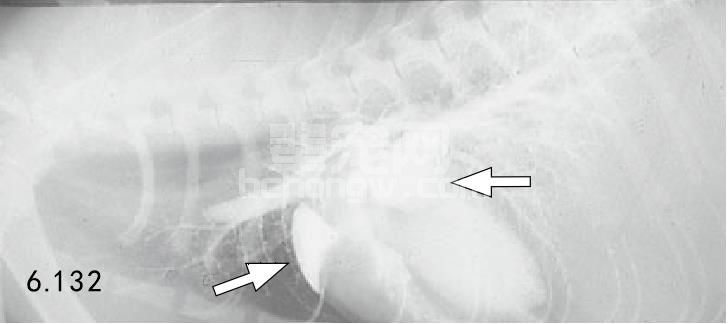

X线片 因为肥大变化是向心的,胸部X线片可能并不明显(图6.130)。由于左、右心房肥大,在腹背位 投影时心脏显现“瓦伦汀(valentine)”形状(图6.131)。这种情形可能发展到左侧或全心肌扩大症。左侧心 衰的猫常常有肺充血和组织间隙性的(而不是肺泡)肺水肿(图6.132和图6.133)。

图6.132和图6.133 患HCM的18月龄的缅甸猫侧位(图6.132)及腹背位(图6.133)对比心血管造 影,显示左心房和右心房肥大(箭头所指)。